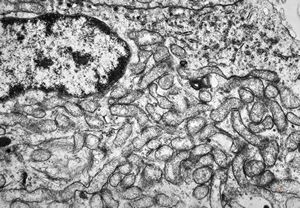

M, 3y. | suprarenal neuroblastoma